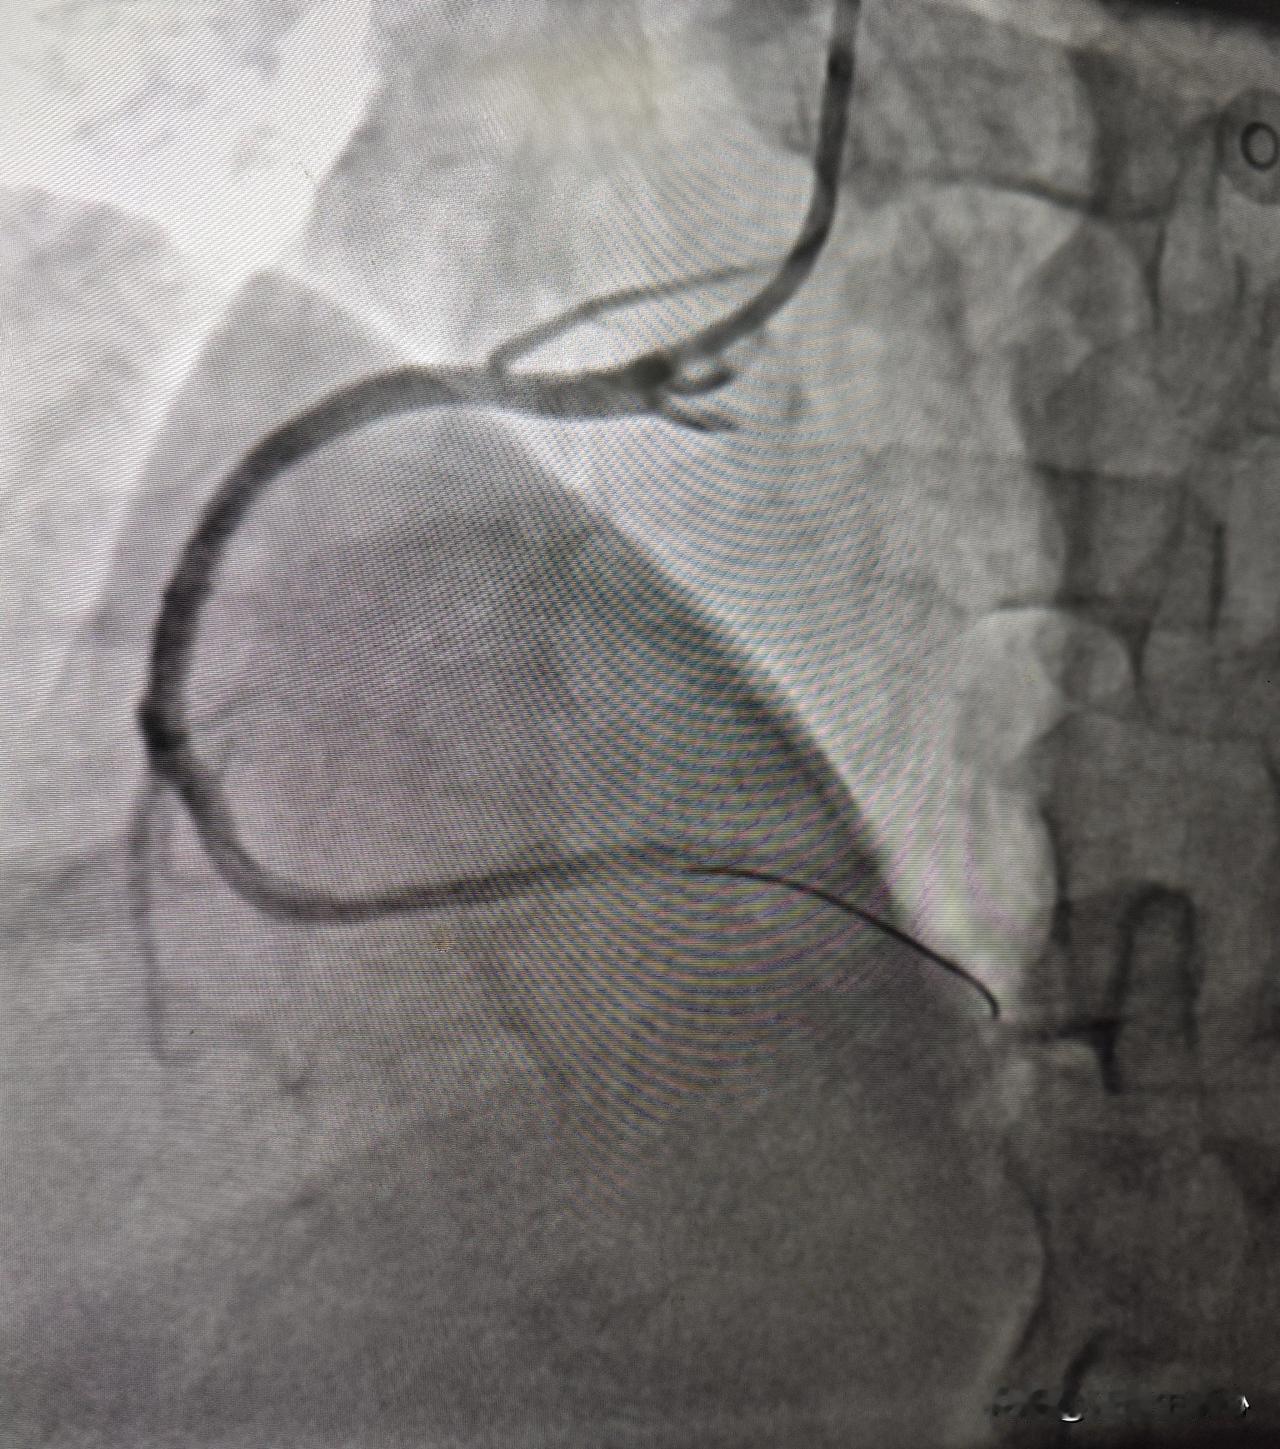

32 岁年轻患者突发心肌梗塞。国庆假期已经接近尾声,刚一接班急诊电话就来了,一个 32 岁男性患者突发胸痛一小时,送到医院做心电图发现下壁导联 ST 段抬高,考虑急性心肌梗塞。赶紧绿色通道直达手术室,一边手术,一边让家属办住院手续,同步进行,争分夺秒,最快速度挽救心肌。 迅速穿刺好桡动脉做冠脉造影检查,发现右冠状动脉重度狭窄,有血栓形成,导丝迅速通过病变部位,用球囊扩张血管,植入支架后血流恢复正常。 这么年轻,血管就一塌糊涂,到处都是动脉硬化斑块,此次急诊手术做了堵塞最严重的地方,还剩做前降支严重堵塞的,等病情稳定以后还需要再做支架手术,听到血管堵塞的位置这么多,这个年轻小伙子一时有点难以接受,又冠心病需要终身吃药,直呼完了完了[流泪] 询问患者有没有什么危险因素,回答说就是抽烟和高血压,其他没了。近几年年轻心梗患者越来越多,跟抽烟、不健康的生活方式关系很大。诸位朋友,不管年龄大不大,健康第一位,保护好自己的心脏。心梗 心梗症状 心梗征兆 心肌梗死